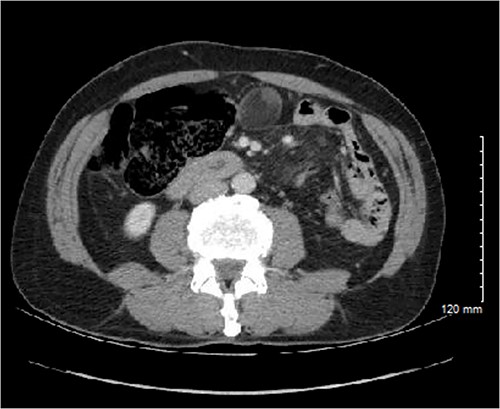

The patient is a 66-year-old male with pertinent medical history including coronary artery disease with recent coronary stent placement who presented to the Emergency Department for evaluation of right flank pain. Cross sectional imaging showed no acute intra-abdominal process; however, an extraluminal, seemingly fat-containing, 3.9 cm mass abutting the cecum and appendix in the midline anterior abdomen was noted (Fig. 1). Differential diagnoses at that time included mesenteric cysts, appendiceal mucocele, nonpancreatic pseudocyst, enteric duplication, epidermoid cyst, and cystic teratoma. Further workup and treatment were unable to be pursued due to elevated risk of bleeding from recent coronary stent placement and antiplatelet treatment with Ticagrelor. Thus, the decision was made for close interval surveillance.

Initial CT imaging showing an extraluminal mass, measuring 3.6 × 3.0 × 3.9 cm with mural soft tissue nodularity within the midline anterior abdomen.